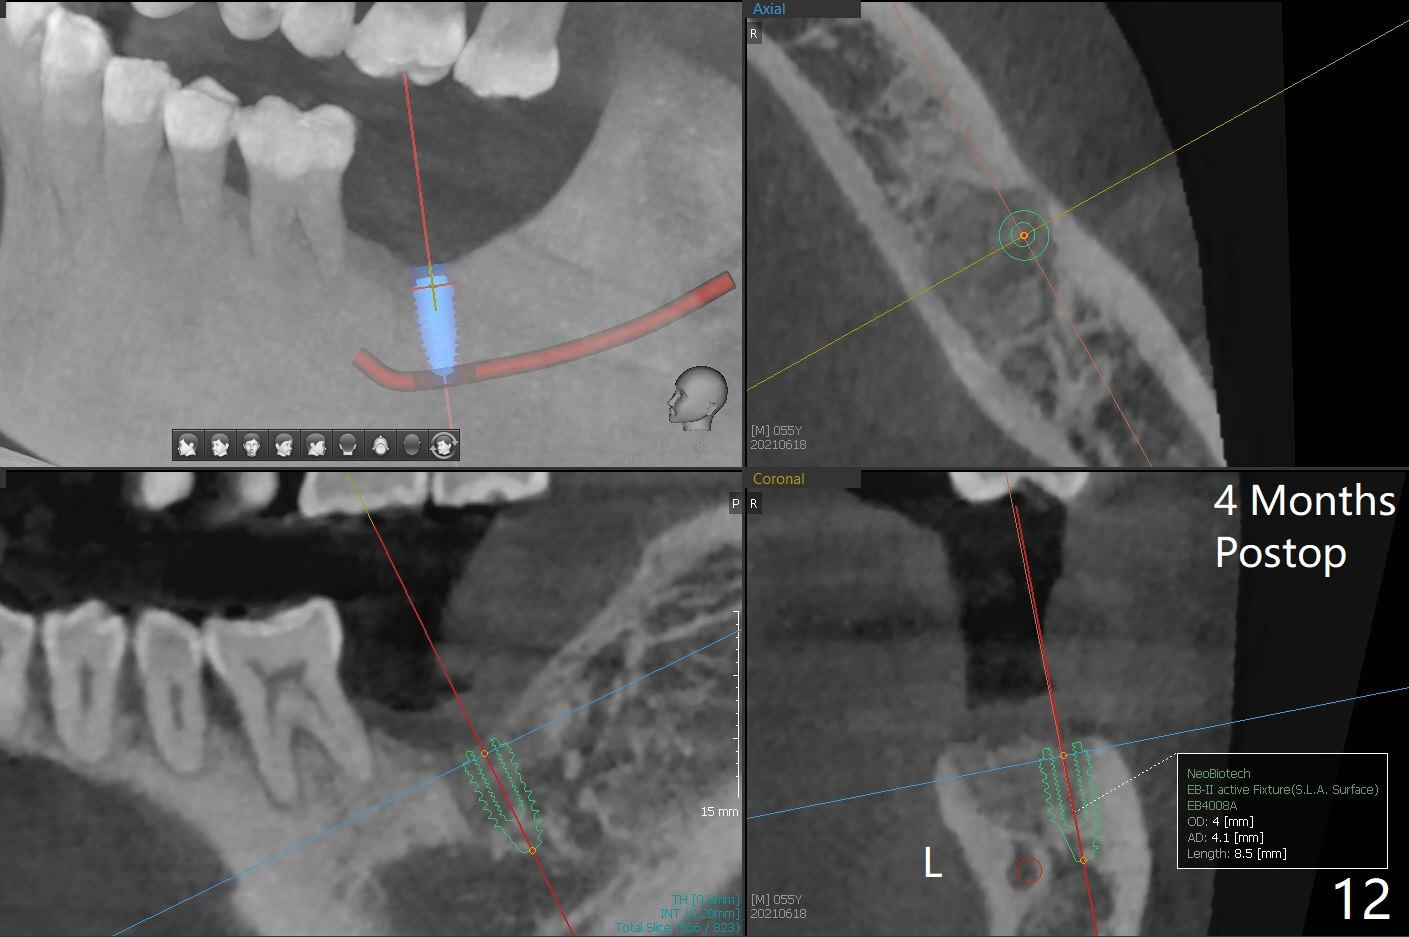

病人回来左下7拔牙植牙,十分感激导板取模后松动牙固位(图一),让他能正常吃饭。去除颊侧树脂和钢丝,6,7之间树脂自动脱落。拔牙后,肉芽组织很多,需要把局麻药注射至肉芽组织中,刮除时不慎远中舌侧牙龈穿孔。尽管纱布压迫,渗血相当多。怀疑导板就位不全,没有纠正。完成钻洞,报废植体无法就位。放置最后一个钻头,根尖片显示钻洞太浅了(图二)。再次磨除6颊侧,远中树脂,导板好像就位,重复钻洞,仍旧太浅(图三),CT表明钻洞偏颊侧(图四)。准备徒手改变钻洞,但是病人疼痛,只好植骨(粘性骨粉)(图五),牙槽窝舌侧,咬合面各覆盖一张PRF膜(图六:箭头),牙间隙维持器和牙周敷料固定。导板在曾经有树脂地方必须缓冲(图七:6;八:*,与图一对比),磨除深度有时不准确。术后两周牙周敷料仍稳定(图九),虽然病人希望撤除,我们偏向保留。反正病人正在做局部牙齿矫正。术后三周牙周敷料脱落,左上6咬合面树脂为了对侧局部牙齿矫正(图十)。骨粉有些丧失(图十一),最好手术时使用不可吸收膜。术后四个月牙槽窝充满骨粉,可以在下齿槽管颊侧植入4x8.5毫米植体(图十二)。